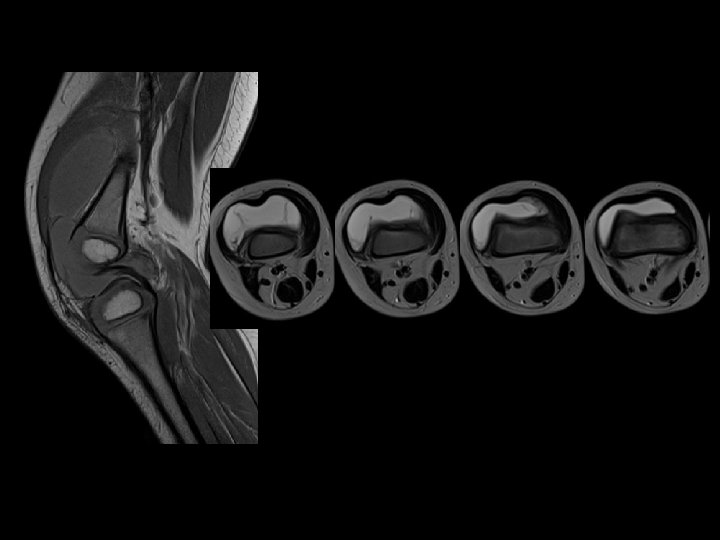

Ménisques • Attention au signal méniscal : plus élevé que chez l’adulte, ressemble à des ménisques dégénératifs d’adultes ! • Avant 12 ans, une image linéaire centrale horizontale est un vaisseau nourricier.

Ménisques • Une lésion méniscale peut révéler un ménisque discoïde • Blocage, pseudo blocage

Gros ménisque en hypersignal